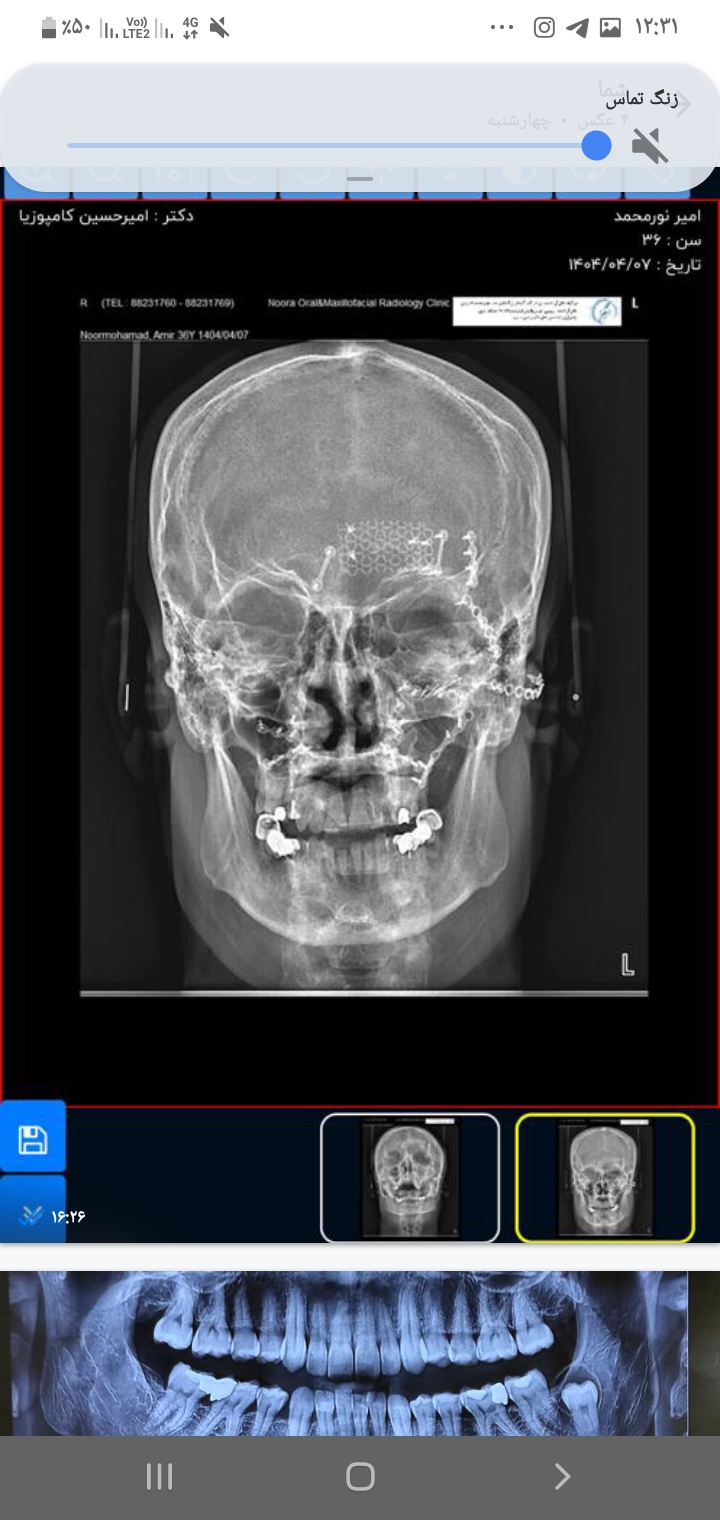

شکستگی متعدد صورت

بازسازی شکستگی صورت